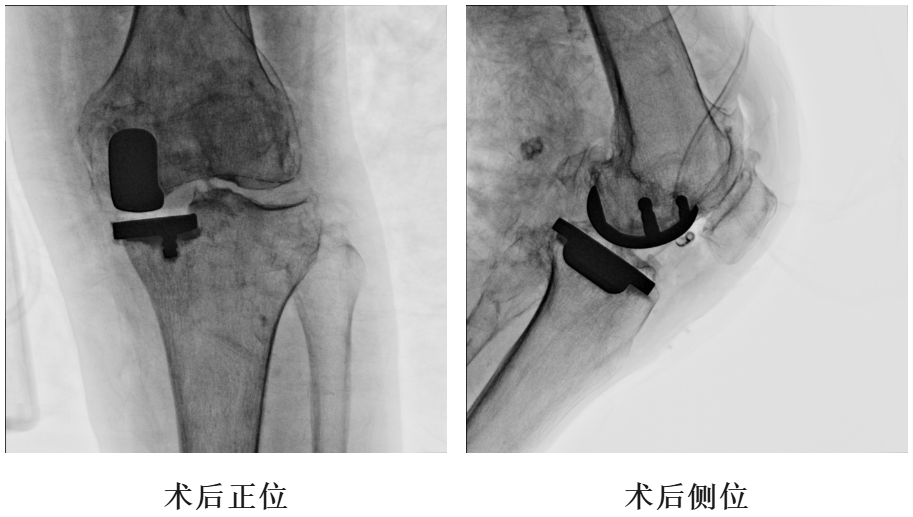

四、术后X片